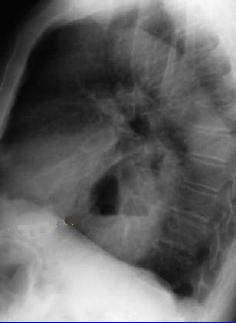

Hernie hiatale : Image

radiologique sans preparation , cliche pulmonaire de

face . Image hydro-aerique a gauche , en arriere le

bord gauche du coeur |